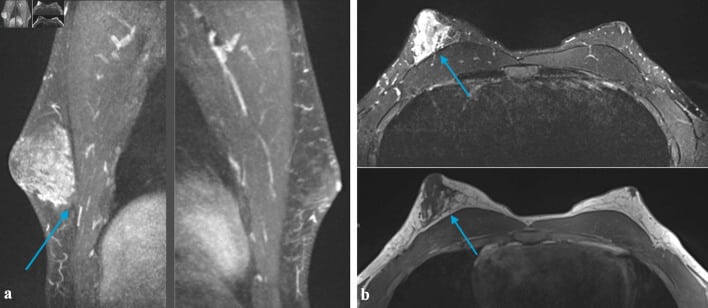

Achados da ginecomastia na ressonância magnética (RM) da mama incluem:

- Presença de áreas de tecido heterogêneo localizadas principalmente na região subareolar.

- Assimetria no volume do tecido mamário, com aumento assimétrico do tecido heterogêneo, podendo estender-se para áreas centrais da mama.

- Ausência de massas suspeitas associadas.

Todavia, esse padrão pode estar relacionado a causas subjacentes, como tumores de células germinativas ou uso de medicamentos.

Por sua vez, os achados sugestivos de câncer de mama na ressonância magnética incluem:

- Presença de lesões de massa com características suspeitas, como margens irregulares ou espiculadas.

- Padrão de realce dinâmico com rápida captação e eliminação do contraste gadolínio (washout), diferindo do realce progressivo típico de lesões benignas.

Além disso, lesões não massivas com padrão de realce em anel aglomerado também indicam maior probabilidade de malignidade, embora apresentem maior índice de falsos positivos.